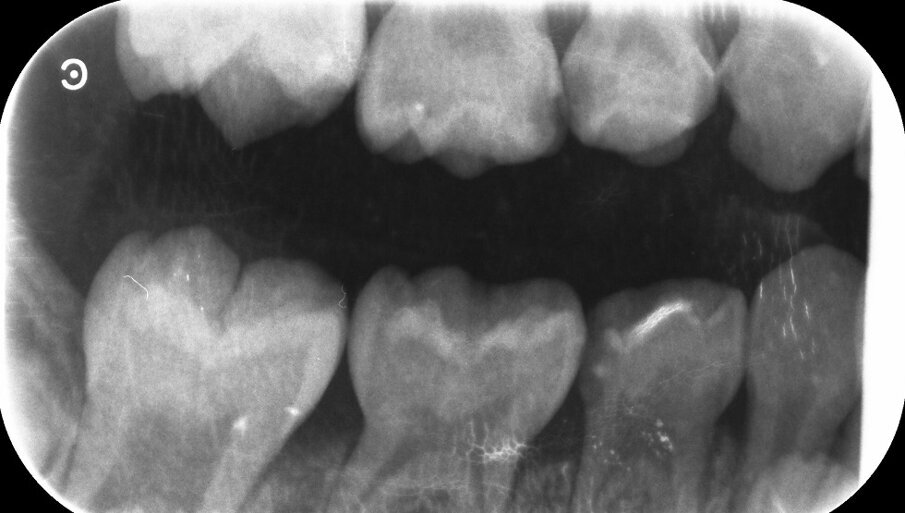

Een ander meisje (6 jaar) kwam op dezelfde wijze in onze praktijk terecht. Ook deze ouders weigerden behandeling onder narcose. Er waren in de pedodontologiepraktijk bitewings gemaakt en ook een weinig fraaie panoramische opname, waarvan ons het nut ontging (afbeelding 5a-b). Wij gingen over tot NRC en het appliceren van zilverdiaminefluoride. Daarnaast werd aandacht aan de suikerrijke voeding besteed. De behandeling was effectief, de laesies stabiliseerden en ruim anderhalf jaar later moest alleen de 65 nog iets worden bijgeslepen wegens toenemende cariësactiviteit. Kort daarna verliet het meisje de praktijk wegens verhuizing naar Saoedi-Arabië.